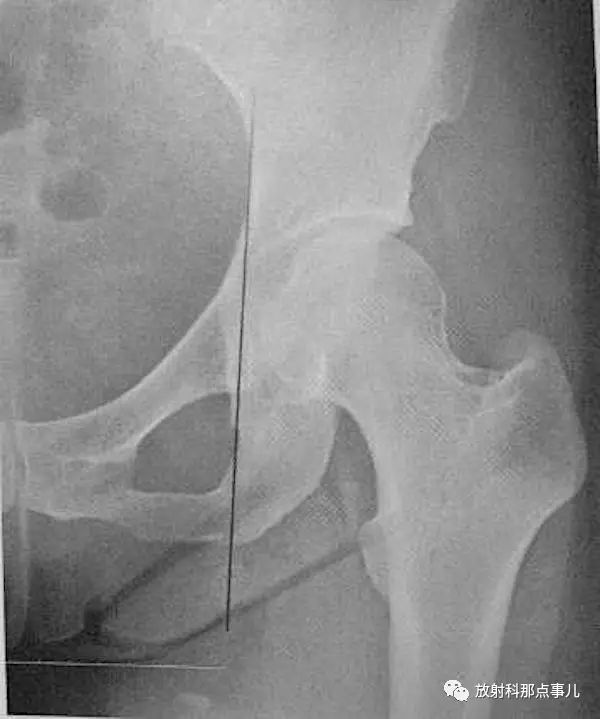

Skinner线

在成人髋关节正位片上,从股骨大转子顶端作股骨纵轴线AB的垂线CD,正常情况下,此线应通过圆韧带窝或其下方,圆韧带窝至上述两线交点的距离是4~5cm。若Skinner线超过圆韧带窝,提示股骨颈或大转子错位骨折。